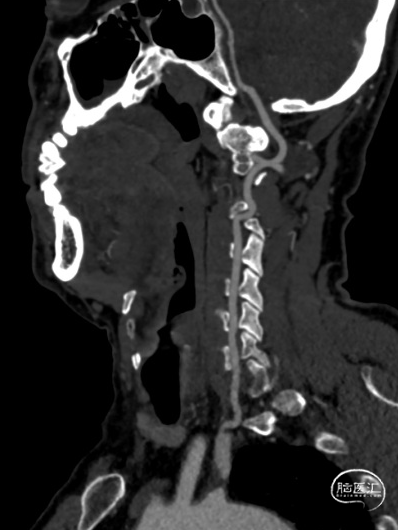

02、术前影像

头颅MR未见明显病灶。

1. 锁骨下动脉闭塞(左侧,伴盗血)

右侧椎动脉造影提示左侧锁骨下动脉盗血,左侧锁骨下动脉闭塞,近端残端较圆钝。